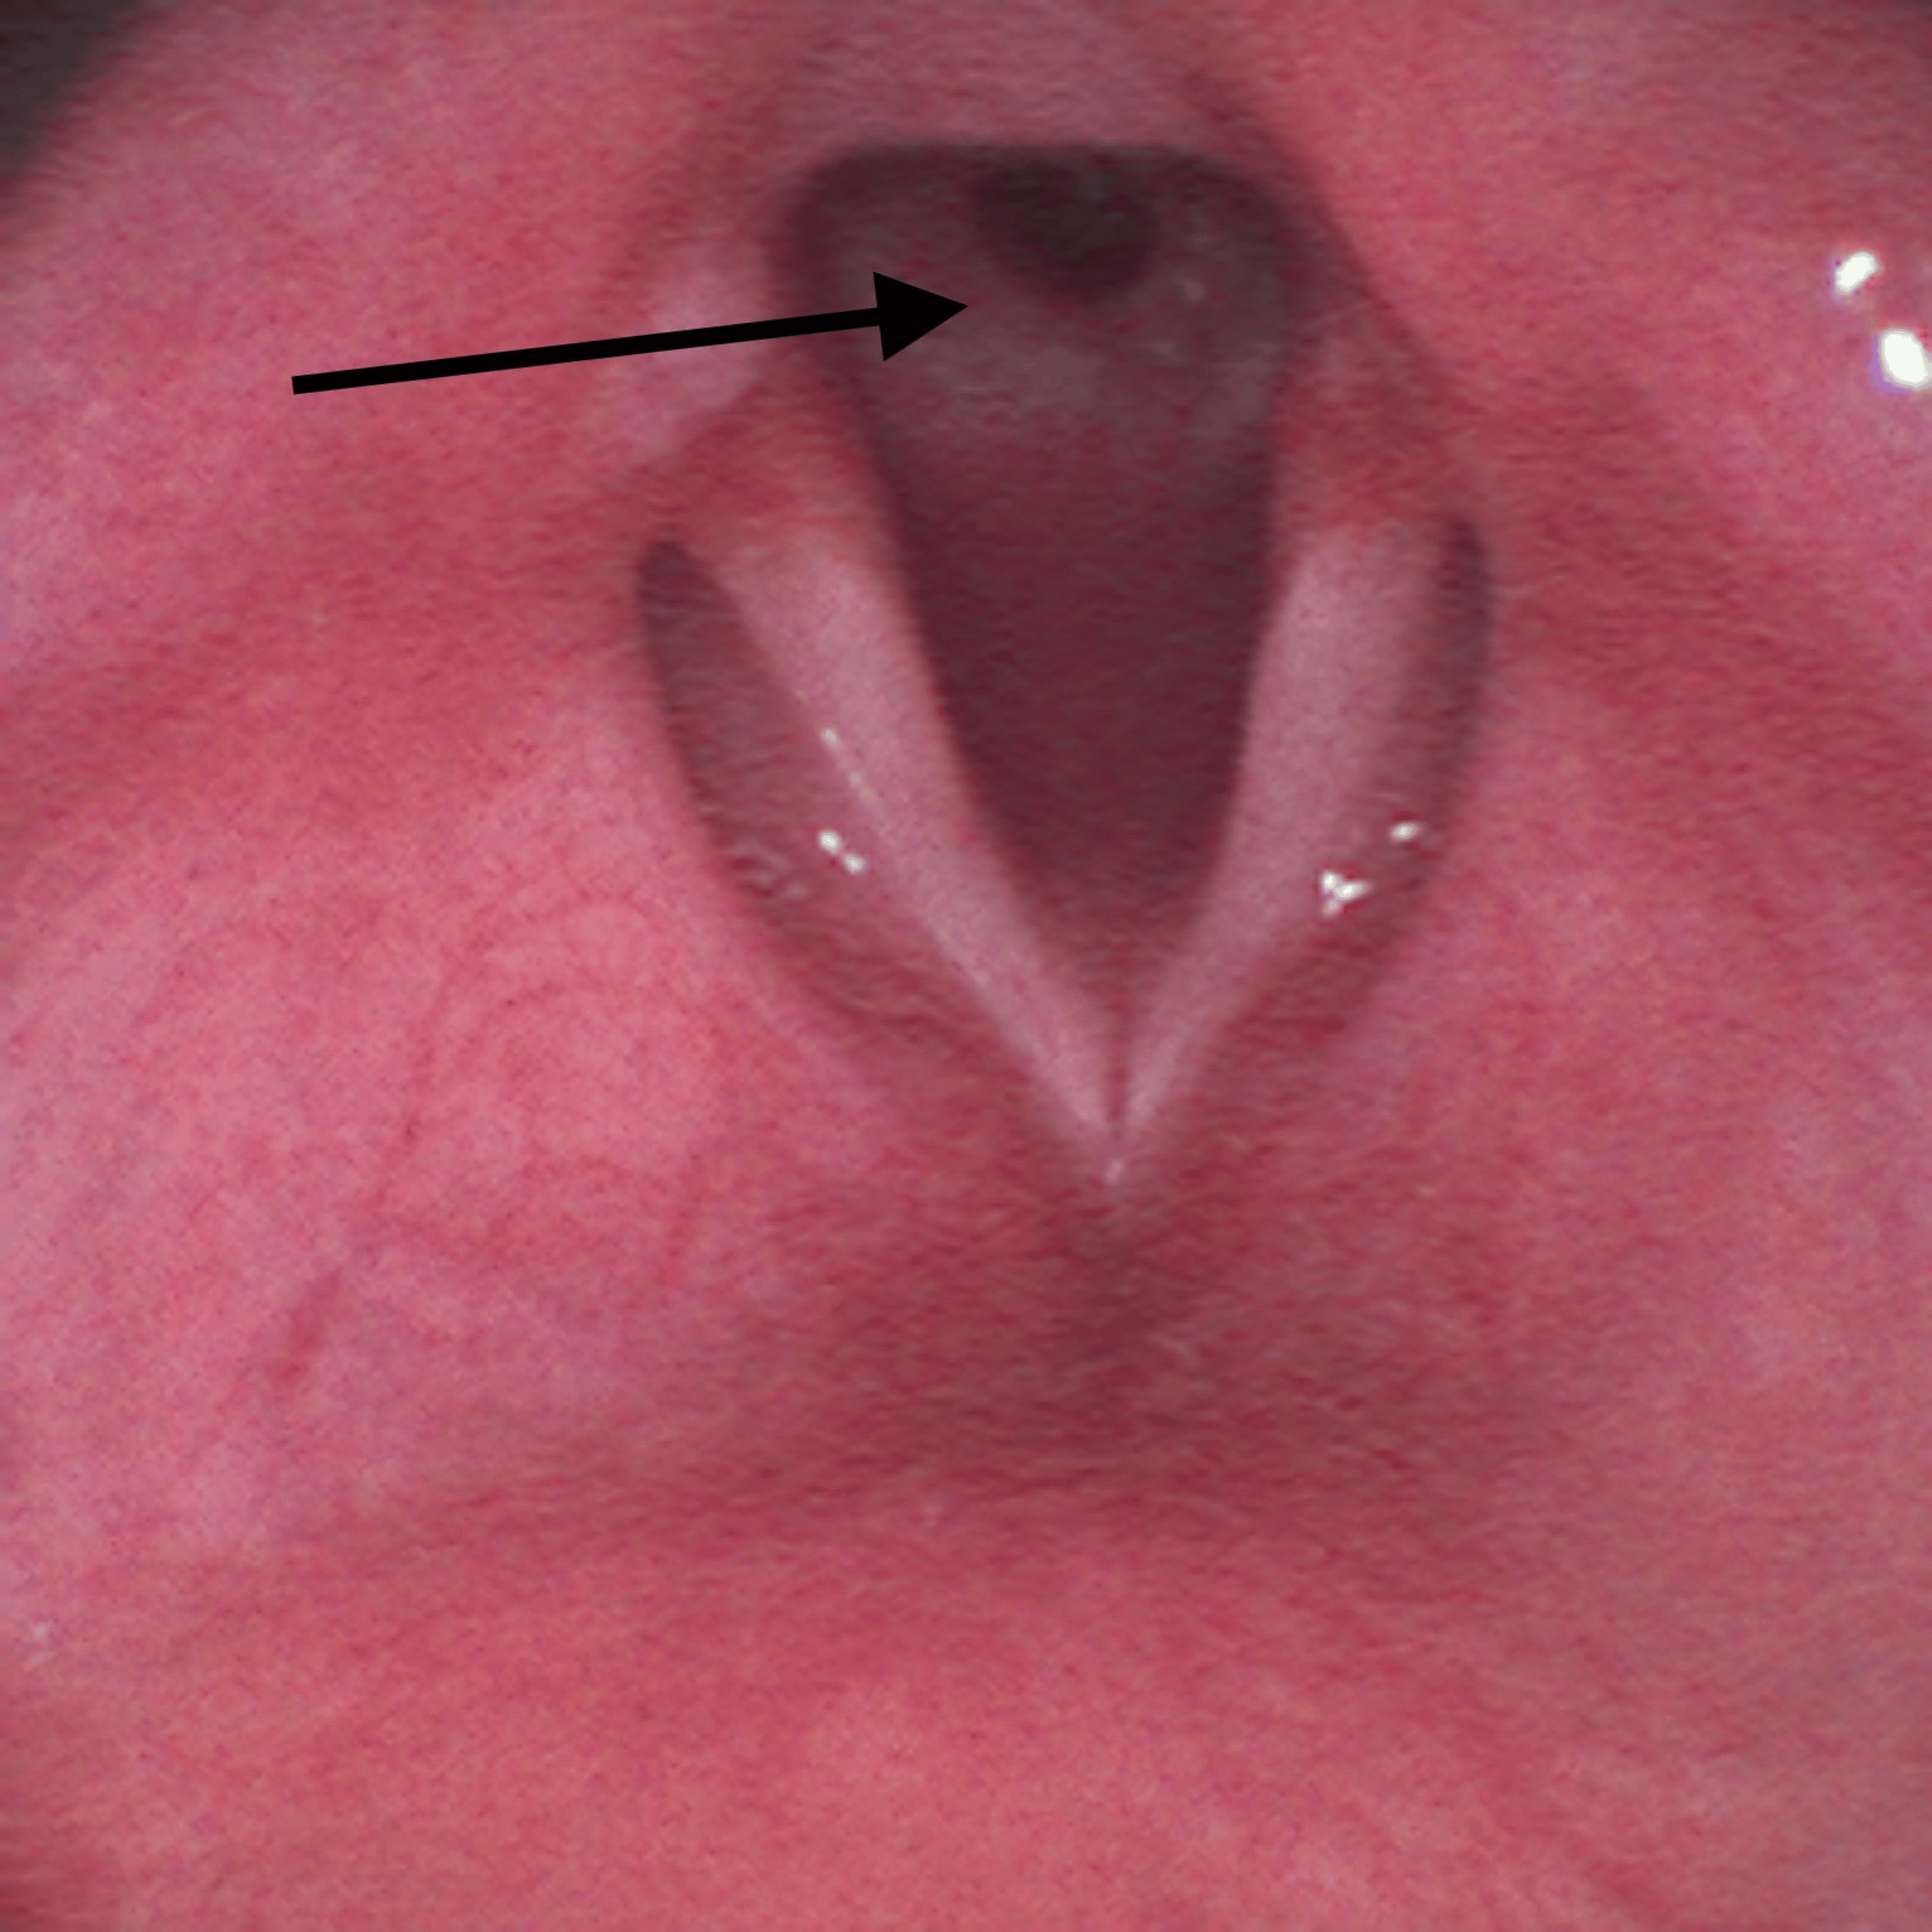

Approximately six months before surgery, he was admitted to a pediatric intensive care unit because of traumatic brain injury with subarachnoid hemorrhage and cerebral contusion. He was under mechanical ventilation/endotracheal intubation for five days, which was the most probable cause for the referred subglottic stenosis. Other relevant previous medical history included Bardet-Biedl syndrome and asthma without recent exacerbations motivating hospital admission. His regular medication included budesonide, formoterol, fenofibrate, and montelukast. He had no medication allergies. Preoperative airway physical examination revealed a grade II Mallampati score, mouth opening greater than 3 cm, thyromental distance of 6 cm, good cervical spine mobility, and a slightly widened cervical perimeter. He mentioned shortness of breath with exertion but during pre-anesthetic evaluation, he was asymptomatic, at rest. Preoperative laboratory results (hemogram, renal function, and coagulation) were unremarkable. Cervicothoracic computed tomography (CT) scan showed a subglottic polypoid formation, 13.5 mm away from the inferior margin of the thyroid cartilage, measuring approximately 3.5 mm in maximum extension and another contralateral polypoid area, very likely consisting of fibrous tissue, with a minimum diameter of 9 mm in the subglottic larynx (Figure 1).

On the surgery day, a reassessment of his airway management plan was performed by a multidisciplinary team including anesthesiologists and otorhinolaryngologists. It was decided to make an asleep fiberoptic visualization of the lesion through a supraglottic device. After adequate pre-oxygenation, endovenous induction was performed using a target-controlled infusion (TCI) of propofol, Schneider model with target effect-site concentration of 4 µg/mL, and of remifentanil, Minto model. A dose of 60 mg of rocuronium was administered and a supraglottic device, AuraGain® size number four was introduced without trauma. Total intravenous anesthesia was maintained using the referred TCI. While maintaining volume-controlled ventilation with a maximum inspiratory pressure of 20 cmH2O, an Ambu® aScope™ 4 Broncho Slim 3.8/1.2 (Ambu A/S, Ballerup, Denmark) was introduced through the laryngeal mask and a circumferential fibrous membrane just below vocal cords was observed (Figure 2).